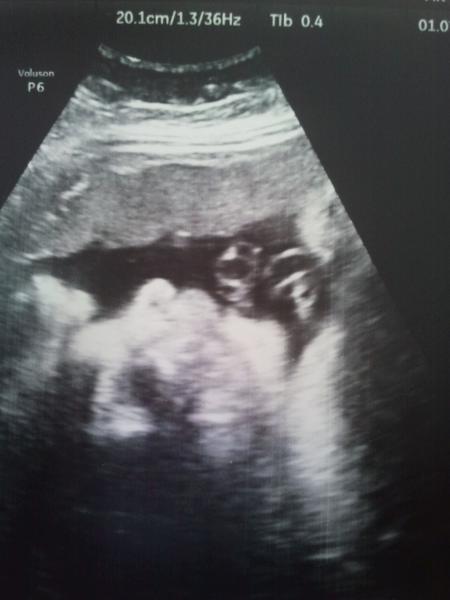

Hallo Mädels, bei uns ist viel passiert in letzter Zeit, Umzug etc. deshalb war ich nicht so oft im Forum unterwegs. Da unser kleiner Schatz in BEL liegt und schon ziemlich fest im Becken sitzt,war ich heute in der Klinik zum Gespräch, da der Kleine in den letzten wochen mit Gewicht und Größe an der oberen Norm lag und ich seit vier Wochen Insulin spitze haben wir uns entschieden einen geplanten Kaiserschnitt zu machen!eigentlicher ET wäre der 2.8. gewesen,die Assistenzärztin meinte erst so ab 22.7., dann hielt sie nochmal Rücksprache mit der Oberärztin und die sagte es sei zu knapp, deshalb der 18.7. mein Freund ist total aufgeregt,und sagte nur dann ist unser kleiner Scheißer ja bald da! Ich werde auch langsam nervös. Bild anbei,vom Profil mit seinen Fäusten! Liebe Grüße Dörte